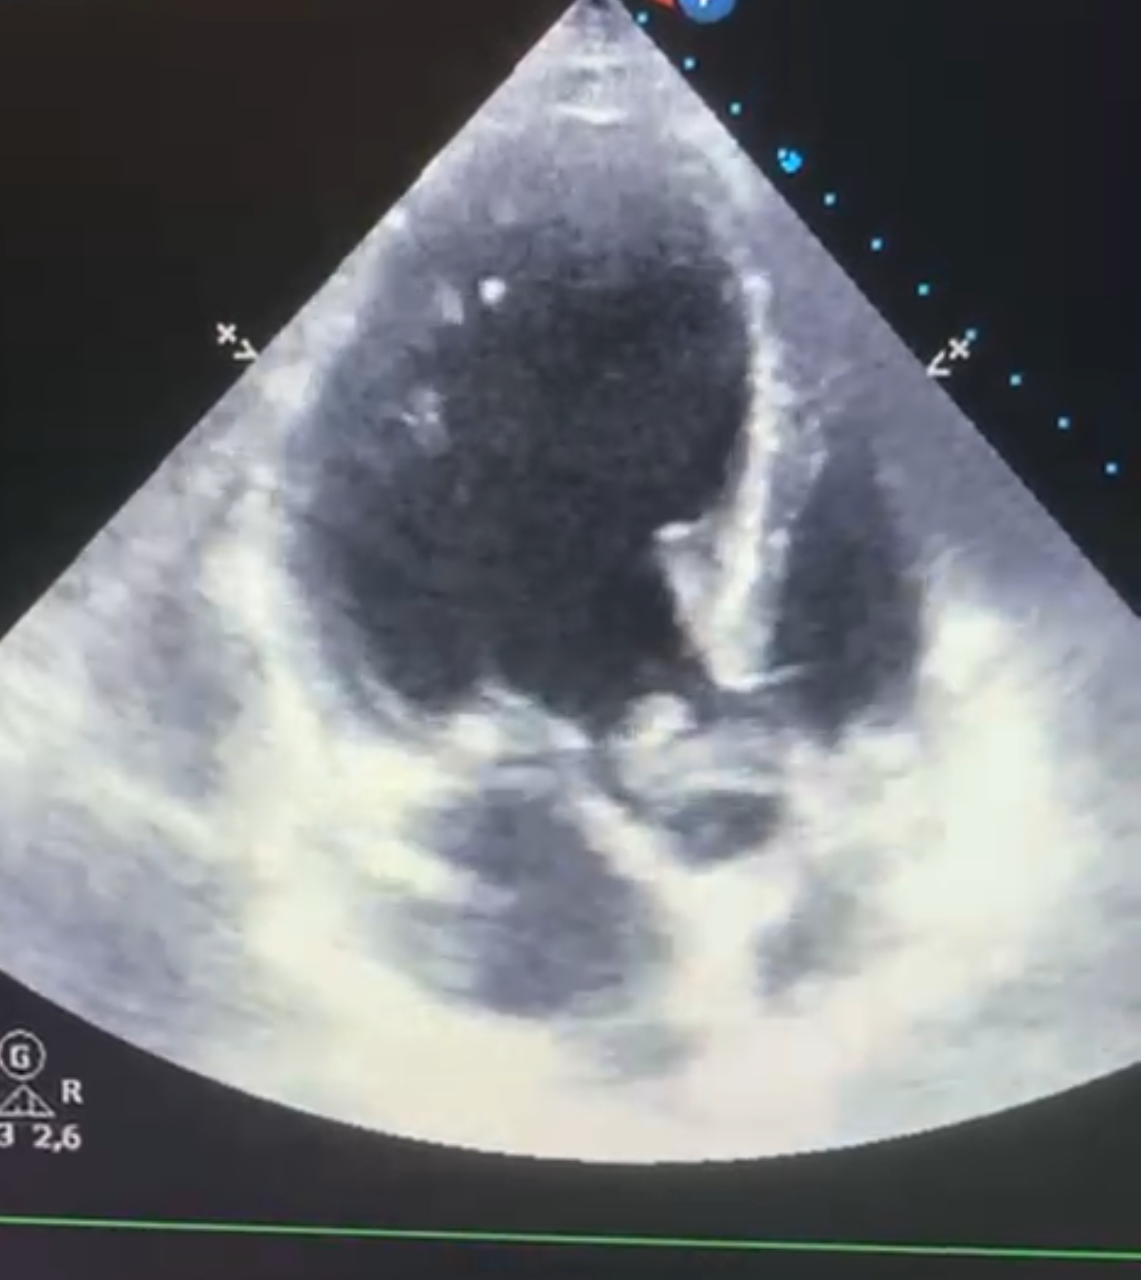

Tras realización de analítica con leucocitosis con desviación izquierda, radiografía de tórax anodina y sin otro foco infeccioso aparente se decide ecocardiografía a pie de cama.

Descripción de los hallazgos ecográficos y las imágenes más relevantes para la resolución del caso

En hemocultivos se detecta Streptococcus anginosus que inicialmente se trata con antibioterapia intravenosa. En TC se visualiza gran verruga en válvula aórtica con insuficiencia severa asociada, por lo que se decide cirugía preferente para recambio valvular.

Ante la presencia de un paciente con clínica inespecífica sin foco infeccioso claro la ecocardiografía a pie de cama ha resultado de gran utilidad para fundamentar la sospecha diagnóstica.